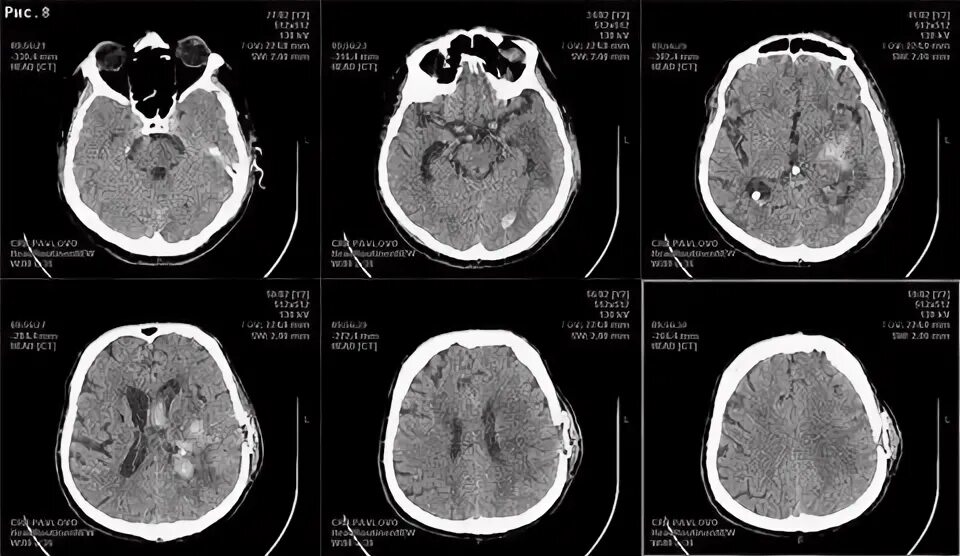

Н 3 кт